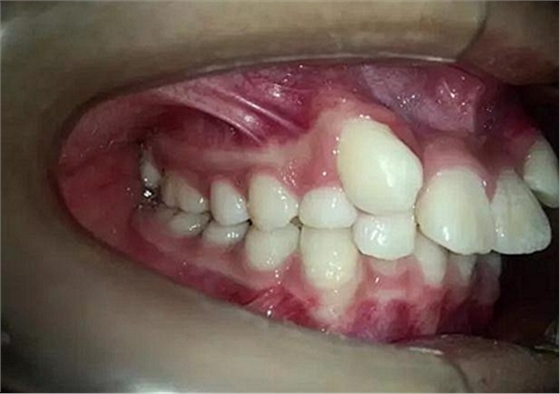

14歲,牙齒嚴(yán)重?fù)頂D,上頜兩個尖牙在側(cè)切牙唇側(cè)

采用細(xì)絲排齊,8字結(jié)扎控制尖牙,此時如果直接拉尖牙,勢必導(dǎo)致上頜磨牙近中移動,更何況磨牙本來就是遠(yuǎn)中關(guān)系,需要強(qiáng)支抗。